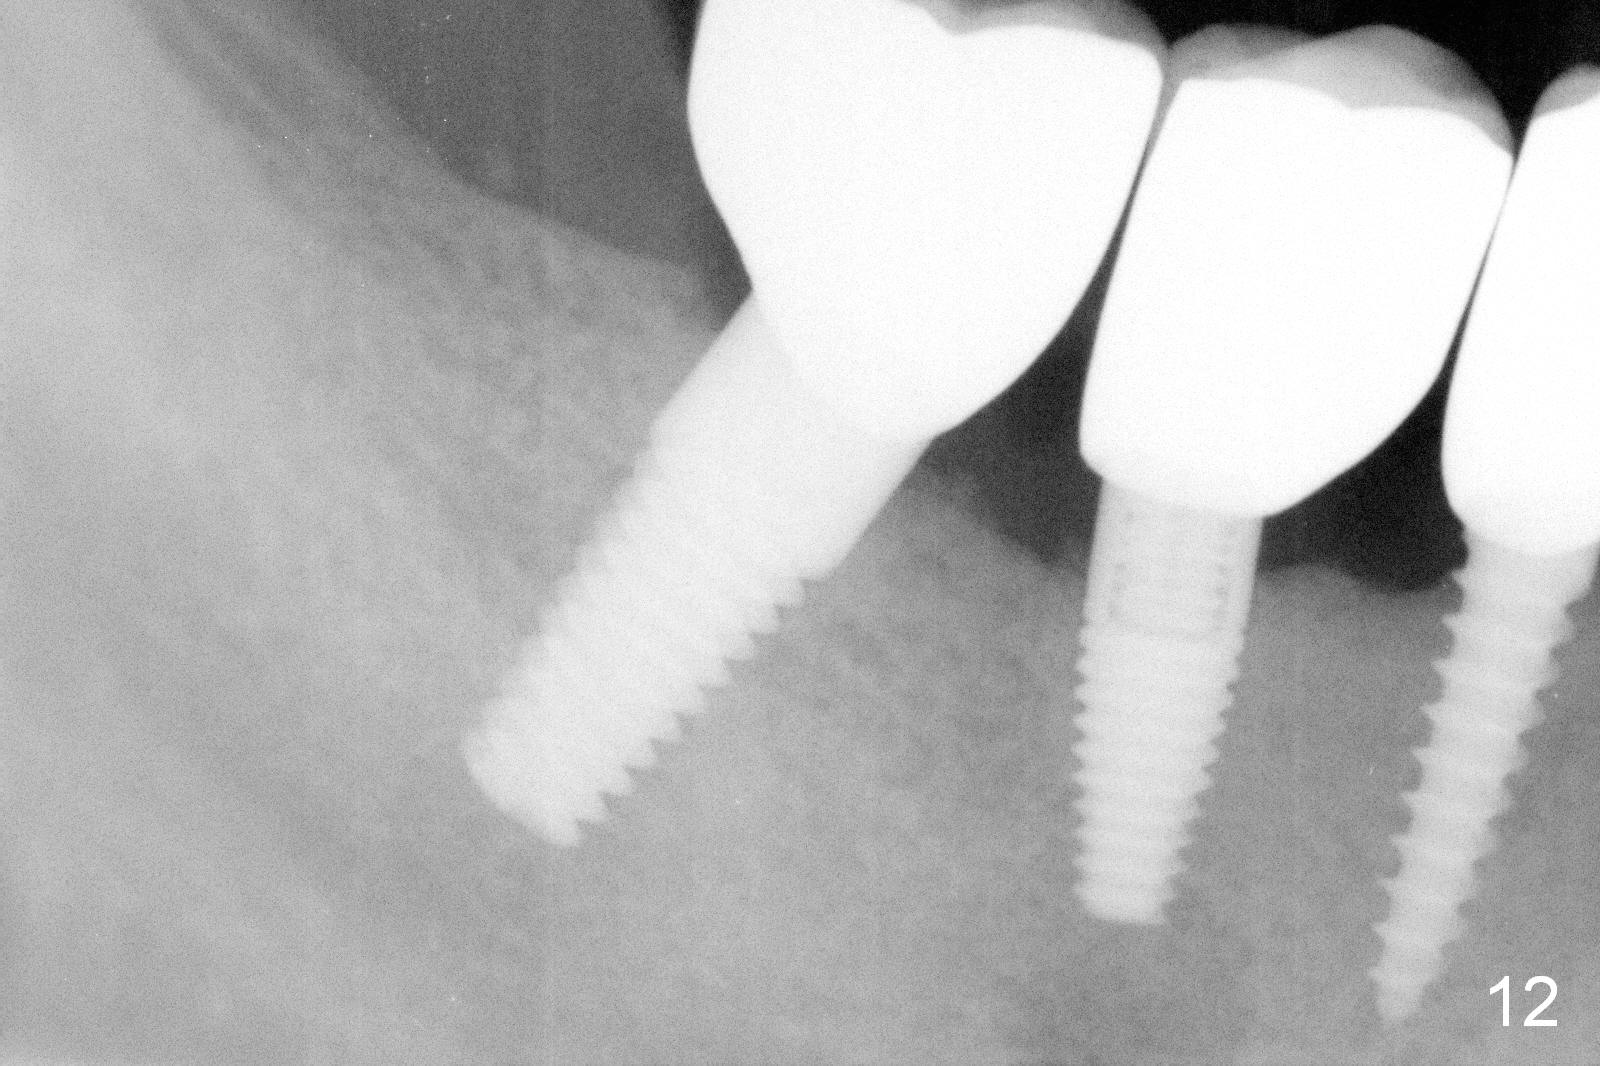

The lower right bridge (from canine (Fig.2: 3) to 1st molar (Fig.1: 6)) fails while a 77-year-old man is undergoing chemotherapy for urinary bladder cancer. The abutments of the bridge are extracted without plan for implants (Fig.4). Four months later, the patient returns for implants (Fig.3), but the ridge is narrow (Fig.5). While 2 of 3x14 mm 1-piece implant are placed at the canine and 1st bicuspid sites, 2 piece ones at the 2nd bicuspid and 1st molar sites (Fig.6: 3.5x11 mm, 5x14 mm). Soft (Fig.7-10) and hard (Fig.11) tissues heal 1 week (Fig.7) and 4 months (Fig.8-11). There is minimal bone resorption 1 year 7 months post cementation (Fig.12,13, non-splinting). It appears that narrow diameter implants are a valid solution to narrow ridge at the sites of the lower canine and premolar. As long as there are enough implants for function, the crowns are not necessary to be splinted. Surprisingly, the patient starts flossing after implant restoration. Retrospectively an immediate provisional bridge should have been fabricated.

There appears to be no bone loss 2 years 5 months post cementation (Fig.14). Gingival bands form around the implants at #27-29 three years 1 month post cementation (Fig.15 *).